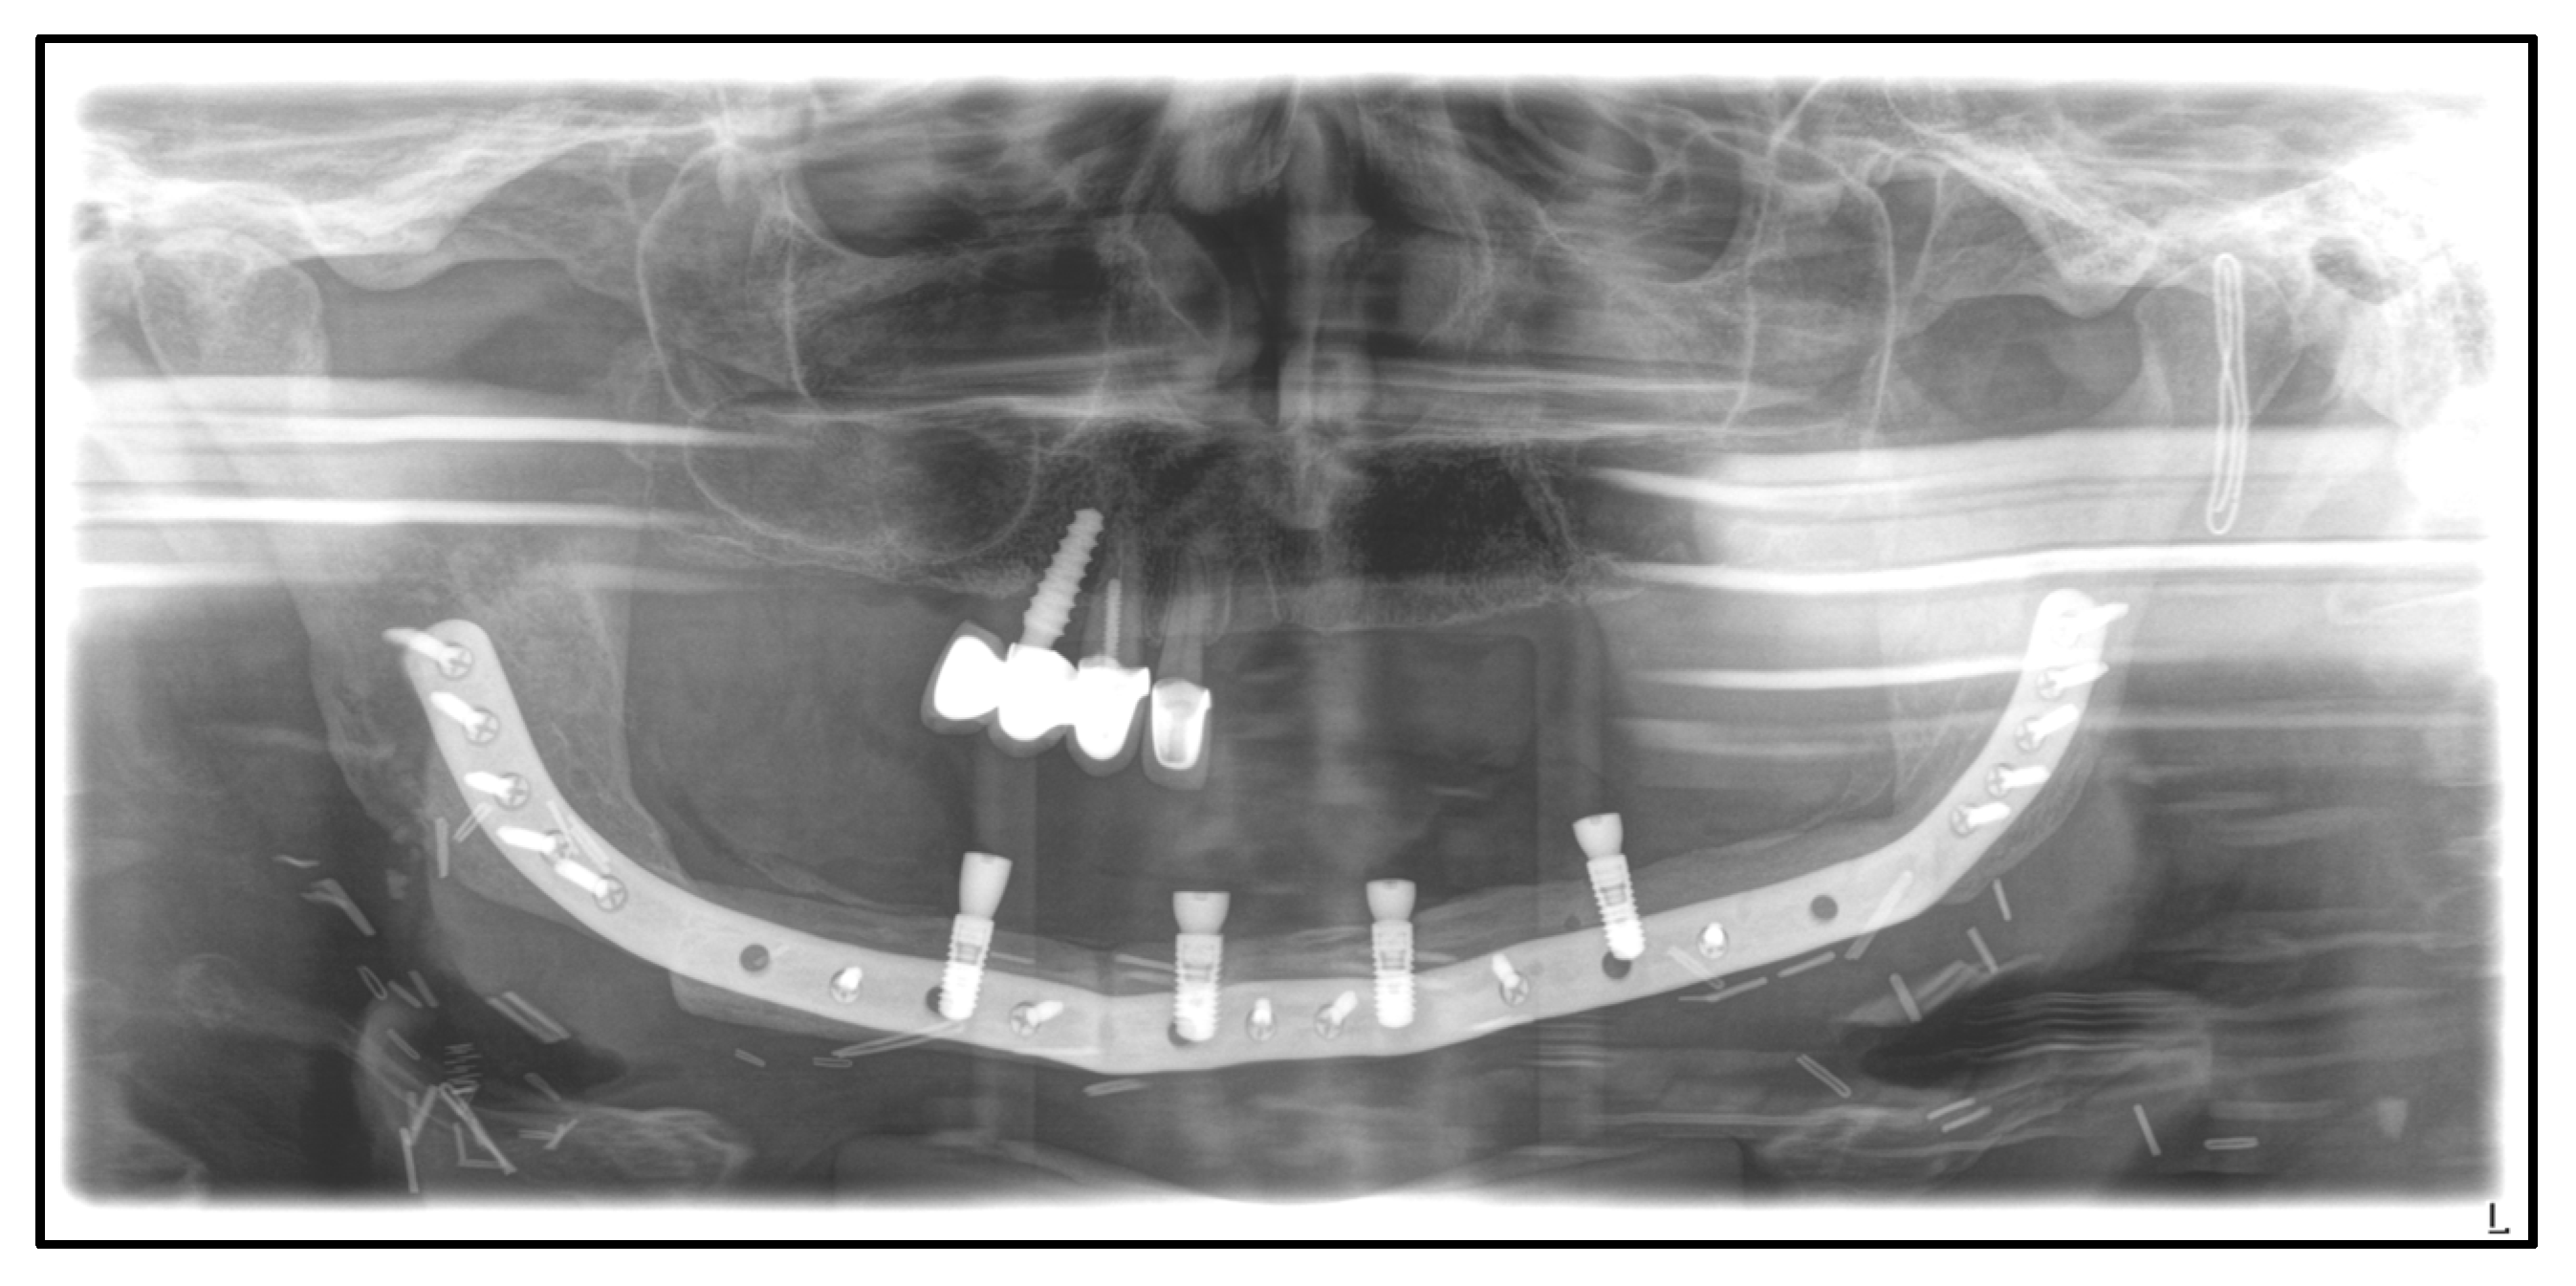

| July 2014: | Diagnosis of MRONJ in the right molar region of the mandible. Following mandibular box resection and protective plate osteosynthesis with a patient-specific plate. |

| August 2018: | Partial mandibular resection with continuity defect and alloplastic reconstruction using a patient-specific plate, excision of a submental fistula |

| September 2022: | Partial mandibular resection from the left mandibular angle to the right mandible, including the right temporomandibular joint, CAD/CAM-guided reconstruction with a bilateral free scapula flap with skin island, and patient-specific plate. In the course: